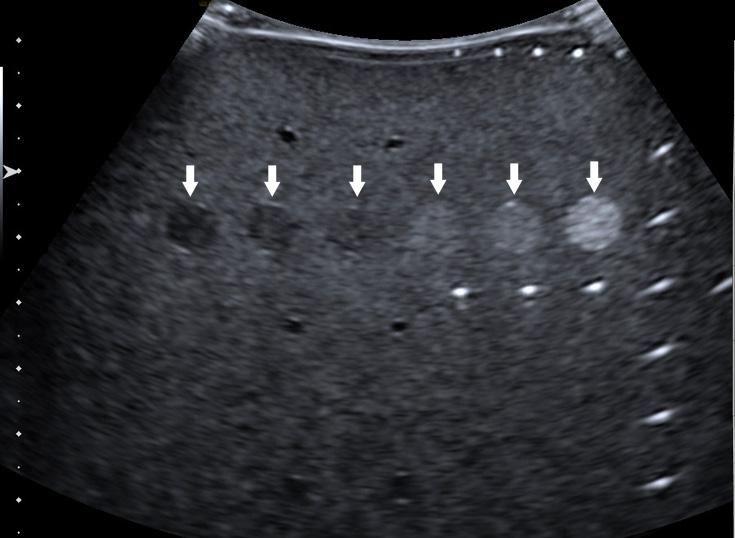

Images obtained during ECRI’s ultrasound scanner testing.

Left: Testing of a needle-enhancement mode. With the mode off (top image), the biopsy needle is barely visible in a soft-tissue phantom; with the mode on (bottom image), visualization is greatly improved.

Right: Visualization of grey scale targets in an ultrasound quality assurance phantom. In this example, all six targets (arrows) can be identified.